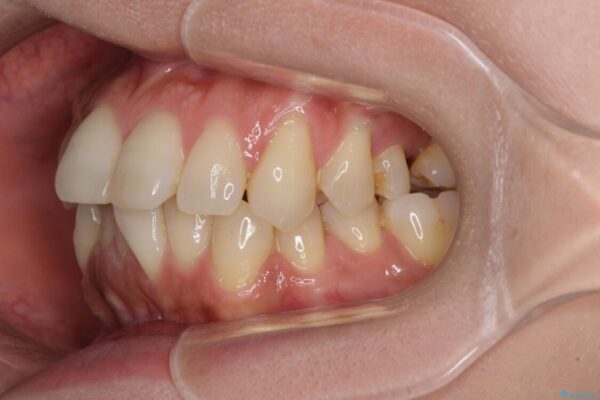

治療前

• インビザラインによる矯正治療と奥歯のインプラント治療 治療前画像

左上第一大臼歯を抜歯した際に、スペースを閉じたそうですが、歯が傾斜してものが挟まって不快とのことでした。

インビザライン矯正で全体の歯列と整えるとともに、左上第一大臼歯部にはスペースを作り、インプラントによる補綴治療を行うこととしました。